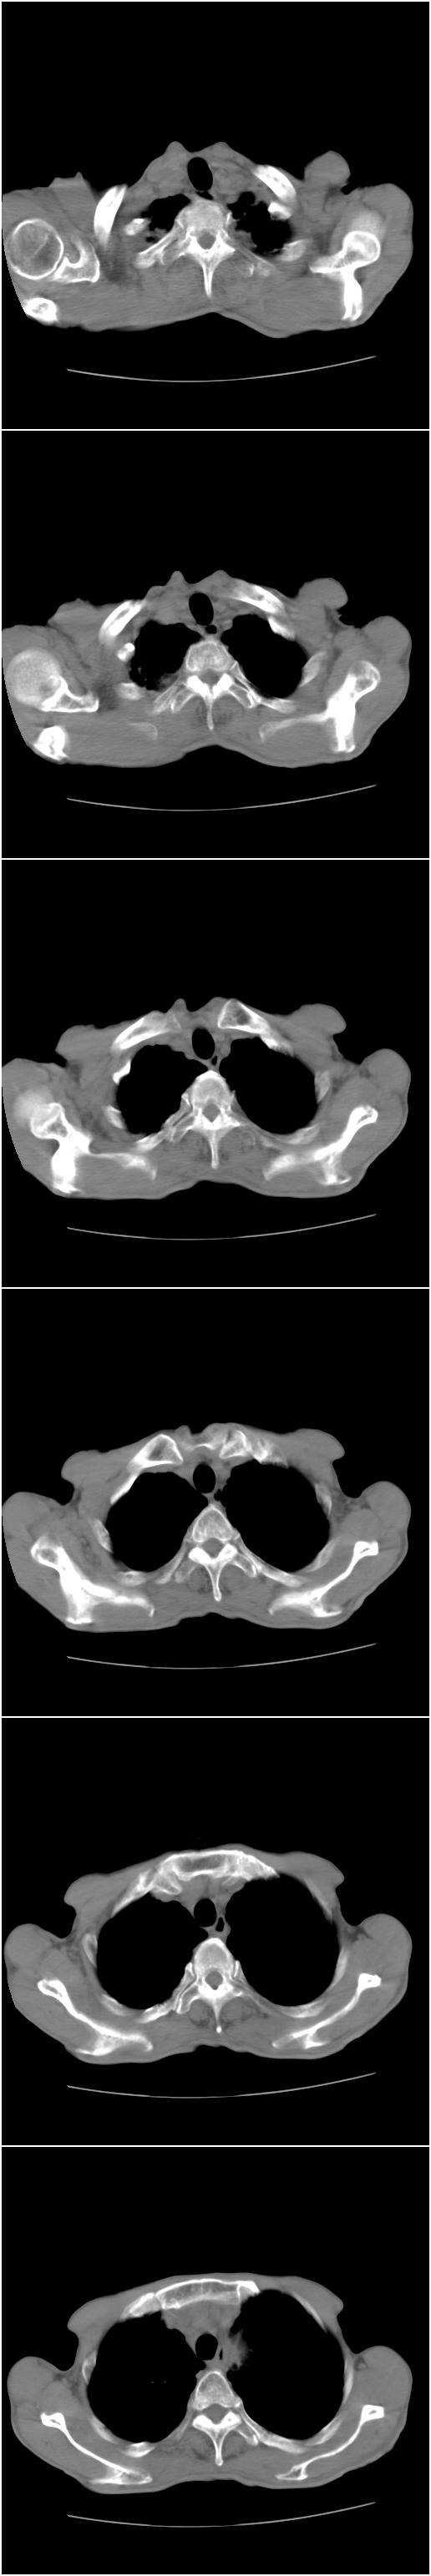

标题: CT12024:男,77岁。咳嗽两月余,气喘一月,13年前岑作贲门 [打印本页]

标题: CT12024:男,77岁。咳嗽两月余,气喘一月,13年前岑作贲门

1、右侧中心型肺癌,右肺门,纵隔淋巴结转移可能性大。

2、贲门癌术后所见。